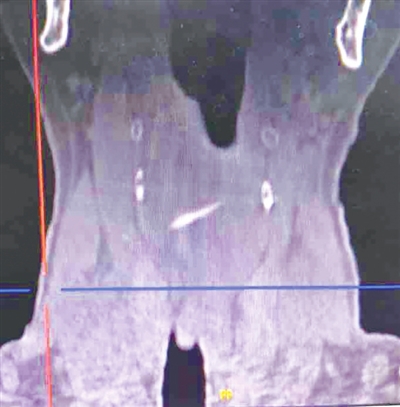

鱼刺在老人体内。

原来,王老太吃晚饭时不小心被鱼刺卡住,家人赶忙带她去当地医院就诊,医生仔细检查后却未能发现鱼刺的踪迹。随后,家人又带着老人前往另一家医院,CT检查显示鱼刺位置较深,医生建议通过胃镜取出。然而,医生操作着胃镜看到鱼刺准备抓取的关键时刻,老人活动了一下,鱼刺竟然不见了踪影,首次取刺行动以失败告终。第二天,经朋友介绍,老人和家人来到城阳区人民医院耳鼻喉科,医生接诊后通过影像学检查发现鱼刺位置比较深,并且鱼刺是从右下斜向左上刺入的,这种情况特别棘手,内镜下很难取出。一旦无法取出,可能需要做颈侧切开来寻找异物。耳鼻喉科医生对影像片子进行仔细分析后,决定在全麻食道镜下进行探查。完善各项术前准备后,麻醉医生成功而快速地让老人进入了理想的麻醉状态,耳鼻喉科团队从左侧梨状窝进食管镜,缓慢向右侧梨状窝移动,避免鱼刺进一步深入组织里,很快就找到了鱼刺的一端,然后再用钳子夹住看到的一端,先向食道方向走行,等把鱼刺完全从组织取出后再通过食道镜完整取出。城阳区人民医院耳鼻喉科副主任杨栋介绍,整个手术过程虽然紧张但很顺利,仅用了3分钟就成功将那根“顽皮”的鱼刺取出。